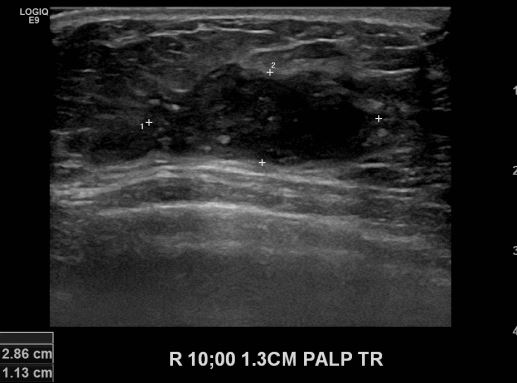

상기환자 우측 유방의 멍울로 내원하신 40대 여성분으로 우측 10시 방향에서 1.3cm

떨어진 거리에 만져지는 멍울 조직검사 시행하여 우측 침윤성 유관암 진단 되었습니다.